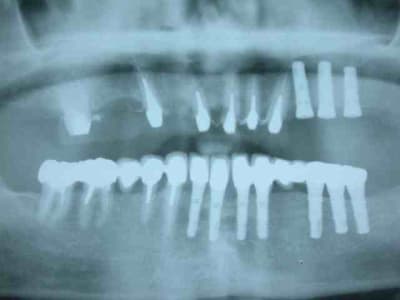

bon allez je vous mets la pano initial et je continue après.

pano après

pose de trois implants en 24 25 26 attente de l'ostéointégration au maxllaire et je poursuis sur la prothèse mandibulaire

bridge transvissé sur 37 36 35 scellé sur fm implantaire sur 32 31 .

couronnes unitaires sur 42 41 (41 mal située position un peu trop lingual : la vue linguale de la photo montre notre solution prothétique pour l'axe)

bridge dentoporté sur 47 46 44 43

pano et photos a suivre les photos sont pas tops car vieil apparei et je vous le rappelle (reflex nauseeux,faut pas aller chercher trop loin quand même , mais vous verrez à la fin on met des écarteurs photos si si...)